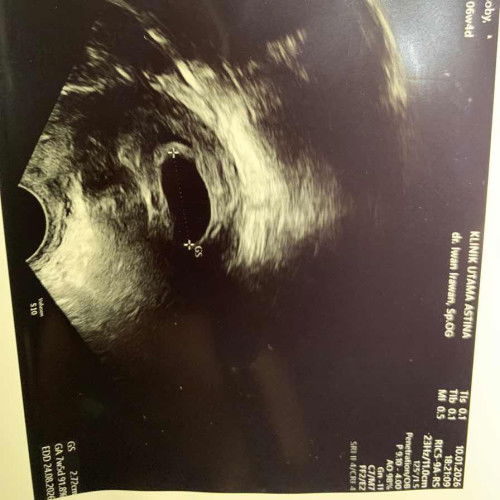

Saya kan haid terakhir itu bln maret thn 2025 posisi saya masih kb suntik 1 bln. Nah bln april 2025 saya lepas kb (itu sdh 1 thn saya kb suntik 1 bln) dan gk haid terus selama thn ini 2026 januari. Tiba2 tgl 6 Januari 2026 saya merasa kram seperti mau haid, iseng2lah tgl 7 aku tespek eh positif jelas bnget, akhirnya tgl 12 Januari 2026 saya usg lah, ternyata usia kandungan ku masih kecil masih 4w6d. Bulan dpn usg lagi buat kontrol untuk memastikan apakah dia berkembang atau tidak. Pertanyaan ku kok bisa ya gk haid lama tp hasil positif, kira2 berkembang gk ya dan kelak bayiku ini gk knp2 kan? Adakah yg punya pengalaman yg sama? Kalau boleh sharing dong krn kejadian ini pertama kali bagiku. Terimakasih.. (Saya sebelumnya sdh punya anak 1 dan pernah keguguran juga anak kedua, jadi skrg anak ke 3) #mohonbantujawabbunda #Sharingdong_Bund #sharing